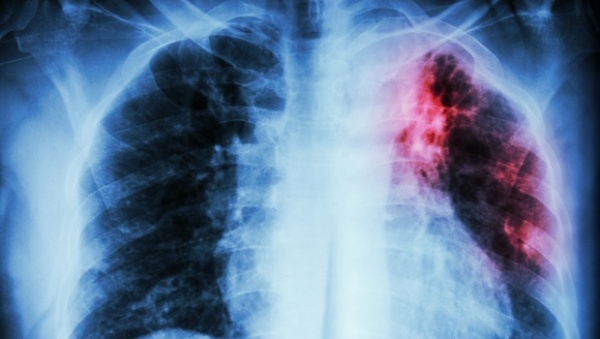

Les données communiquées par Dr Oumellil, relatives à la région Ouest, font état d’une baisse de l’incidence de la tuberculose, toutes causes confondues (pulmonaire et extra-pulmonaire), passant de 76 cas pour 100.000 habitants en 2013 à 67,2 cas/100.000 hab en 2016.

Selon cette même responsable, une nette amélioration est observée pour les deux types de tuberculose, avec une incidence établie en 2016 à 31,5 cas/100.000 hab pour la pulmonaire (contagieuse) et à 35,6 cas/100.000 hab pour l’extra-pulmonaire (non contagieuse).